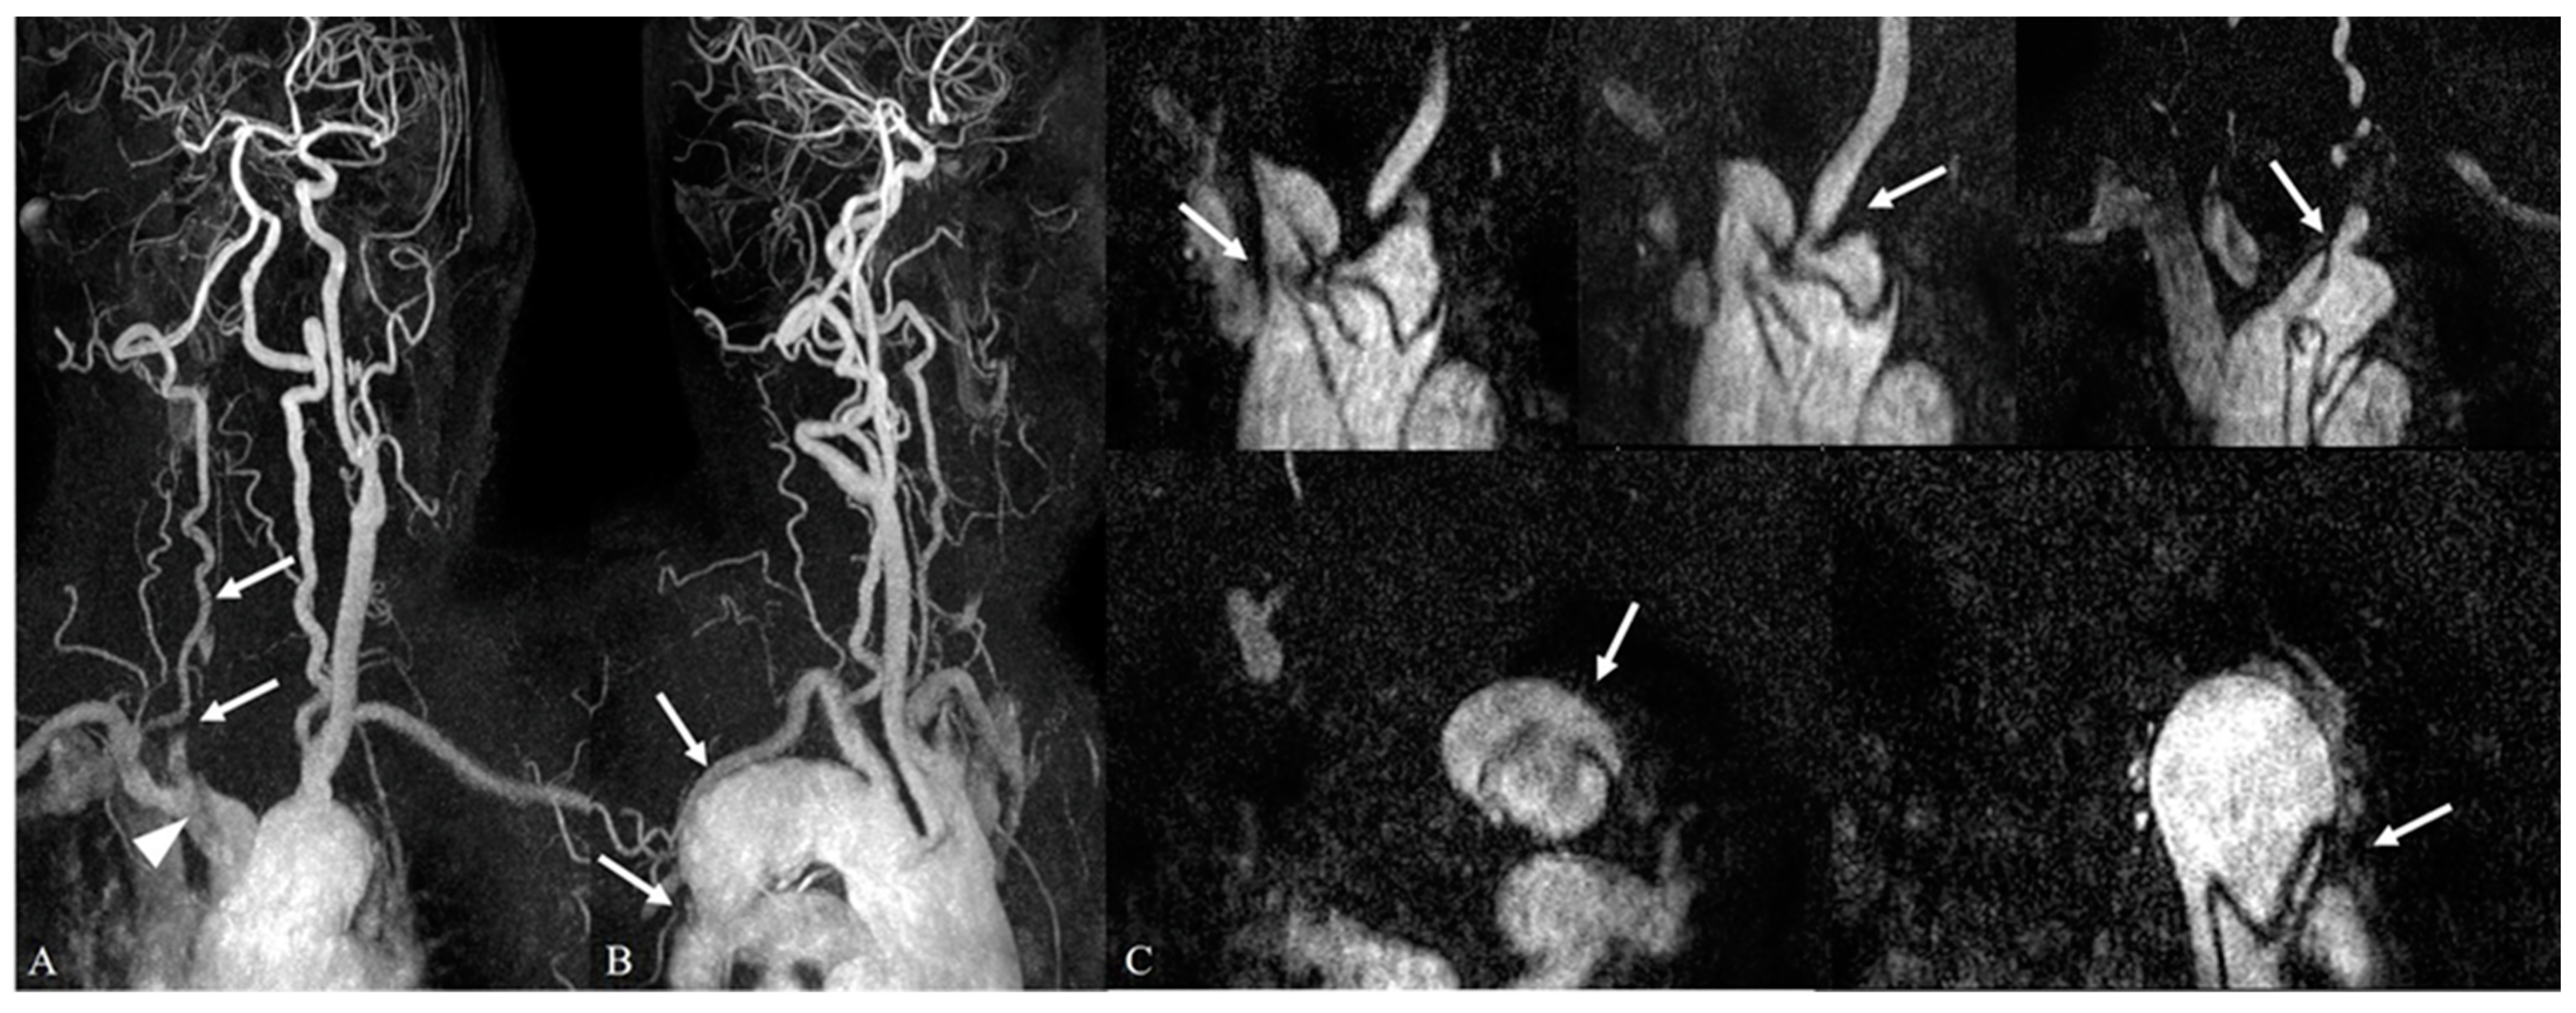

3.2. Incidental Aortic Arch Abnormalities on Contrast-Enhanced Neck MR Angiography

| Category II (Minor or no significant findings) | 319/348 (91.7%) | 331/348 (95.1%) |

| Direct aortic arch origin of vertebral artery | 280/348 (80.4%) | |

| Aberrant right subclavian artery | 39/348 (11.2%) | |

| Common trunk | 8/348 (2.3%) | |

| Right-sided aortic arch | 4/348 (1.2%) |